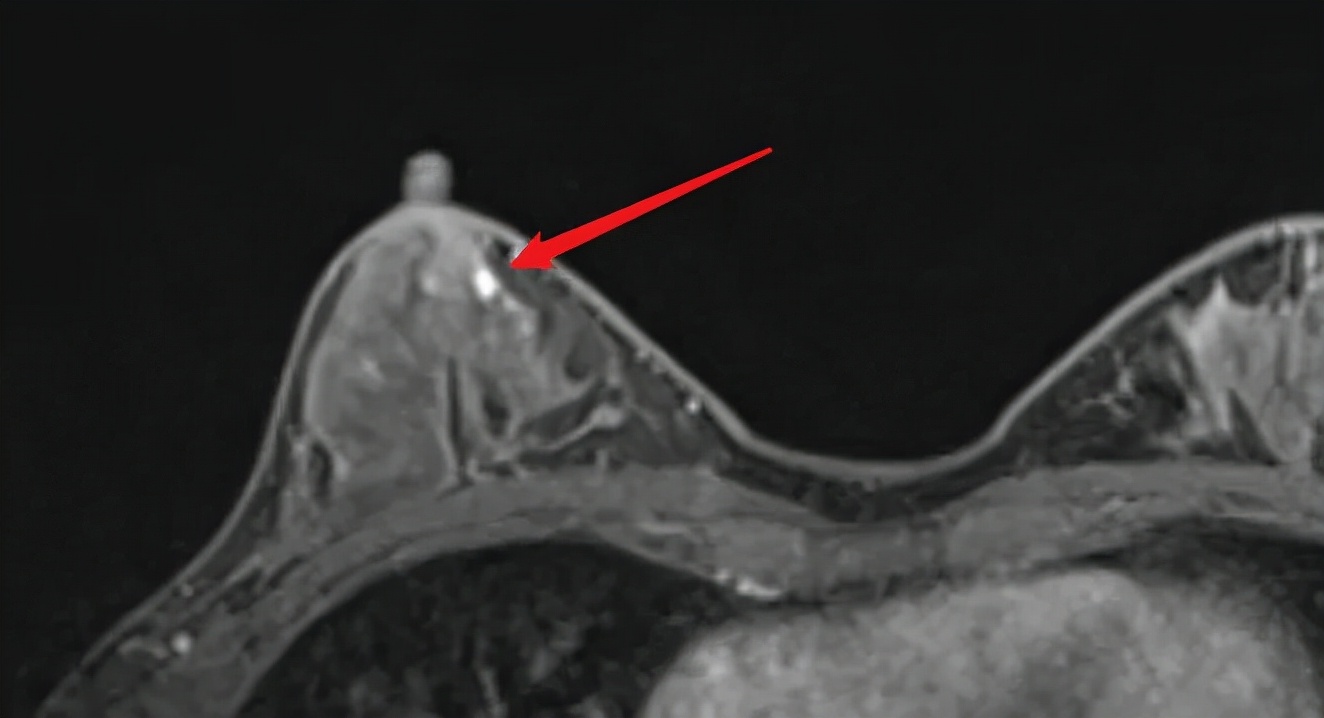

仔细检查患者后,我发现患者右乳乳晕区质地较左侧偏硬,右乳晕触诊病灶与钼靶发现的钙化灶位置不一致;MR报告为BI-RADS 3类,但我发现患者乳晕下方、与乳管相连有一个增强结节,因此建议患者手术。估计患者事前已了解过BI-RADS 3类是良性可能大,因此想先回老家过年、年后做手术。

MR发现右乳晕与乳管相连结节

我与患者一起解读MR,并告知:我感觉乳晕下乳管内结节不舒服,至少是导管内乳头状瘤,目前虽然没有乳头溢液,但乳晕下乳管结节迟早会增大、会出现乳头溢液,甚至会发生异变,如果你不同意手术、最多只观察3月,但我建议你马上手术治疗!